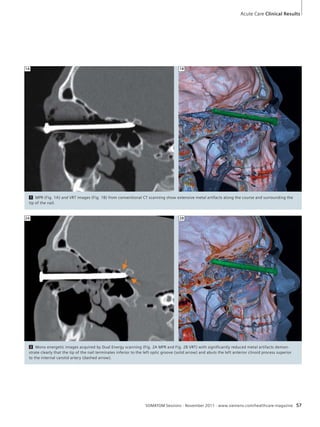

56 SOMATOM Definition Flash:

Metal Artifact Reduction with

Mono Energetic Dual Energy

Imaging in a Critical Trauma Case